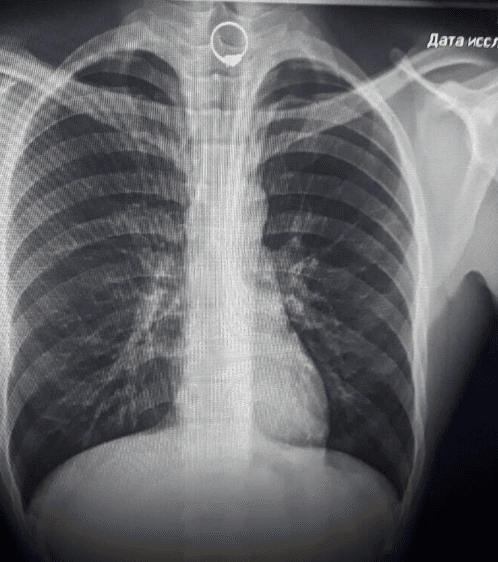

Згодом правоохоронці затримали нападника в одному з ломбардів, однак при затриманні він проковтнув одну з викрадених каблучок.